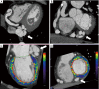

Axial and basal short axis CT images representing the coronary arterio-venous fistula (white arrow). The vessel carries out tortuous kinkings before reaching the crux cordis (A,B); (C,D) perfusion maps: long axis and short axis views representing the inferior defects near fistula and the anterior defects in myocardium supplemented by LAD. LAD, left anterior descending artery.